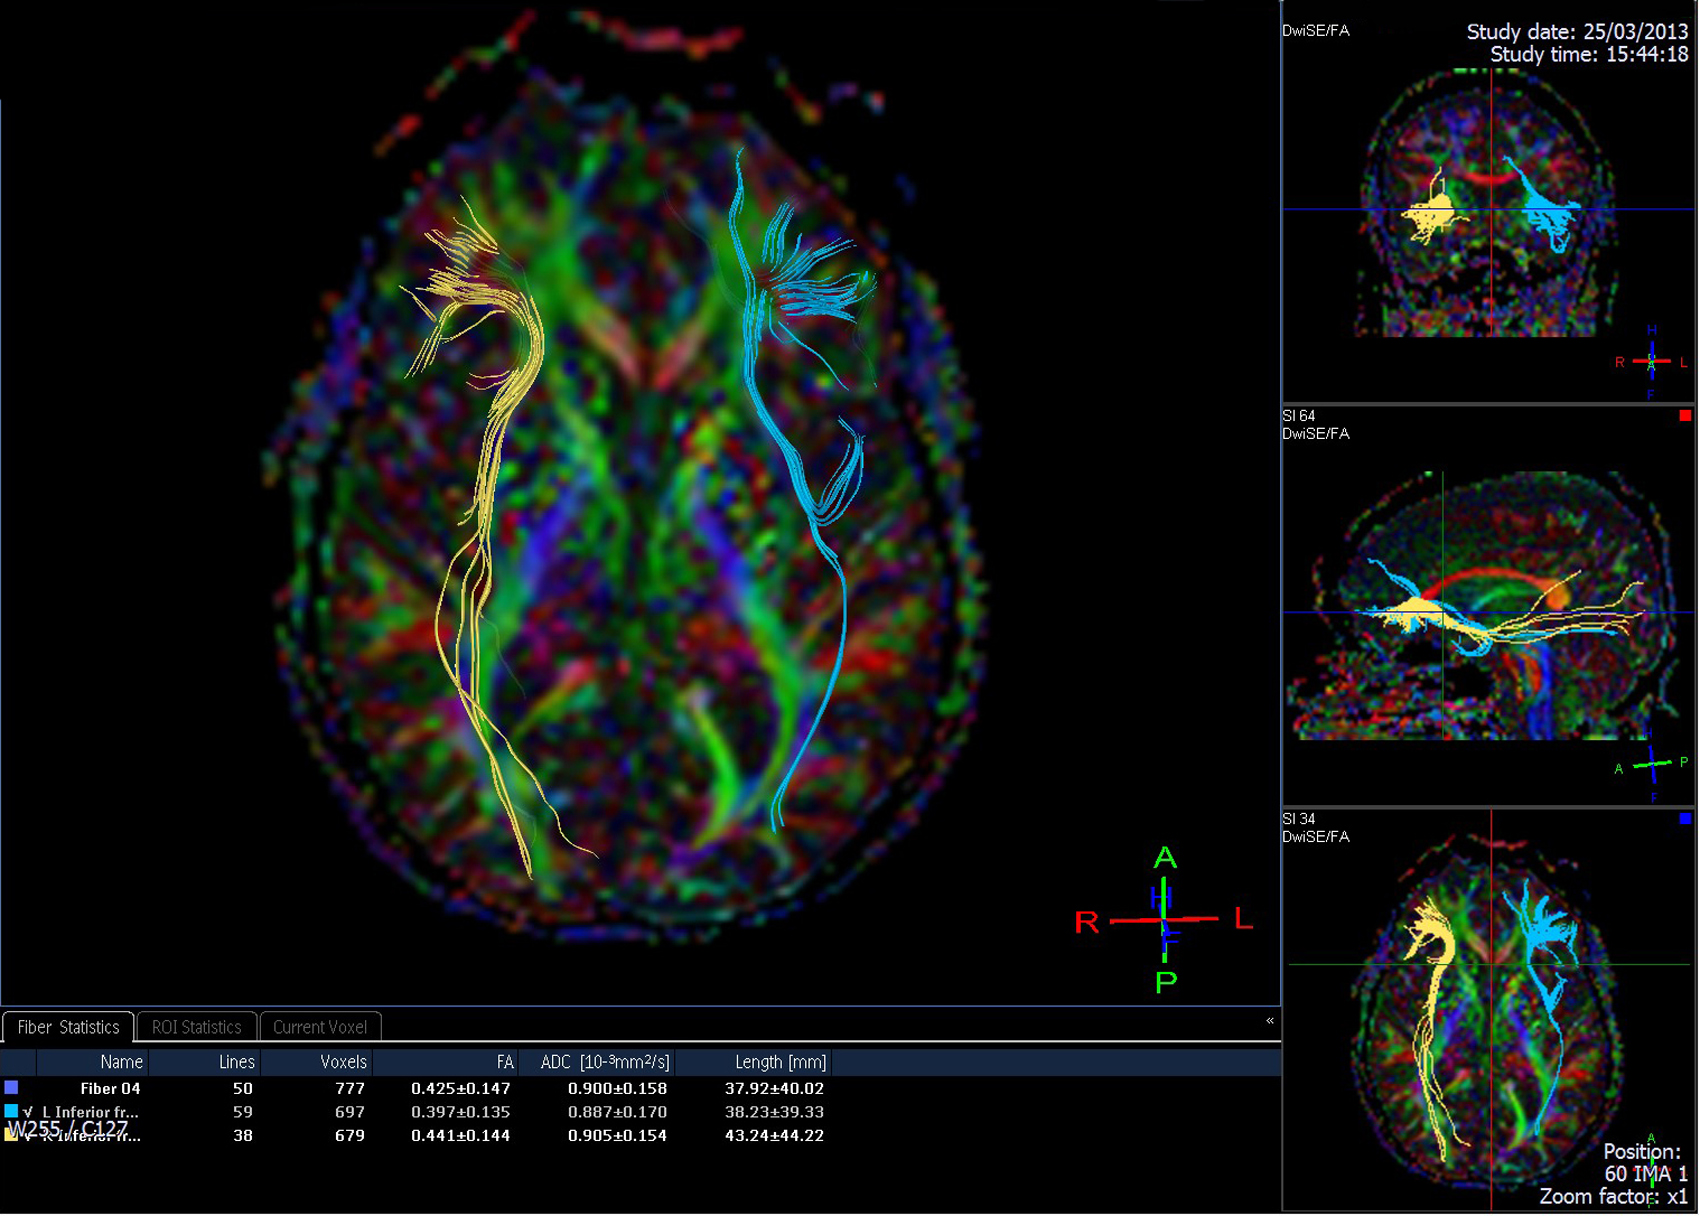

Studies show that structured literacy based reading programs don’t just improve reading skills—they can actually rewire the brain. White matter, which connects different regions, becomes stronger and better organized with the right kind of reading practice.

Children and adults with dyslexia may have less organized pathways for phonics and fluency. The great news? Structured-literacy based interventions can strengthen these pathways and make reading easier over time.